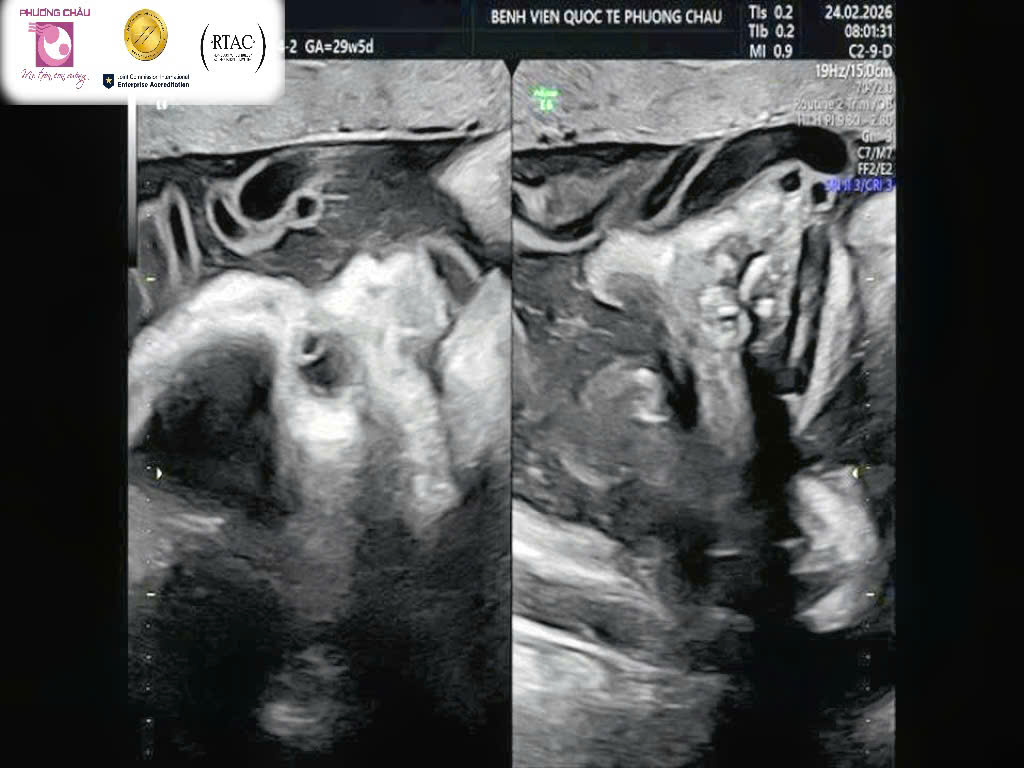

Hội chứng da vảy cá trên siêu âm (nguồn: Bệnh viện Quốc tế Phương Châu)

Do mức độ nghiêm trọng, phần lớn trẻ mắc hội chứng da vảy cá rất khó sống sau sinh, chủ yếu do các biến chứng như suy hô hấp và nhiễm trùng nặng.

Thông thường, Hội chứng da vảy cá có thể được phát hiện qua siêu âm hình thái vào 3 tháng giữa thai kỳ bởi các bác sĩ siêu âm có nhiều kinh nghiệm và chuyên môn cao.